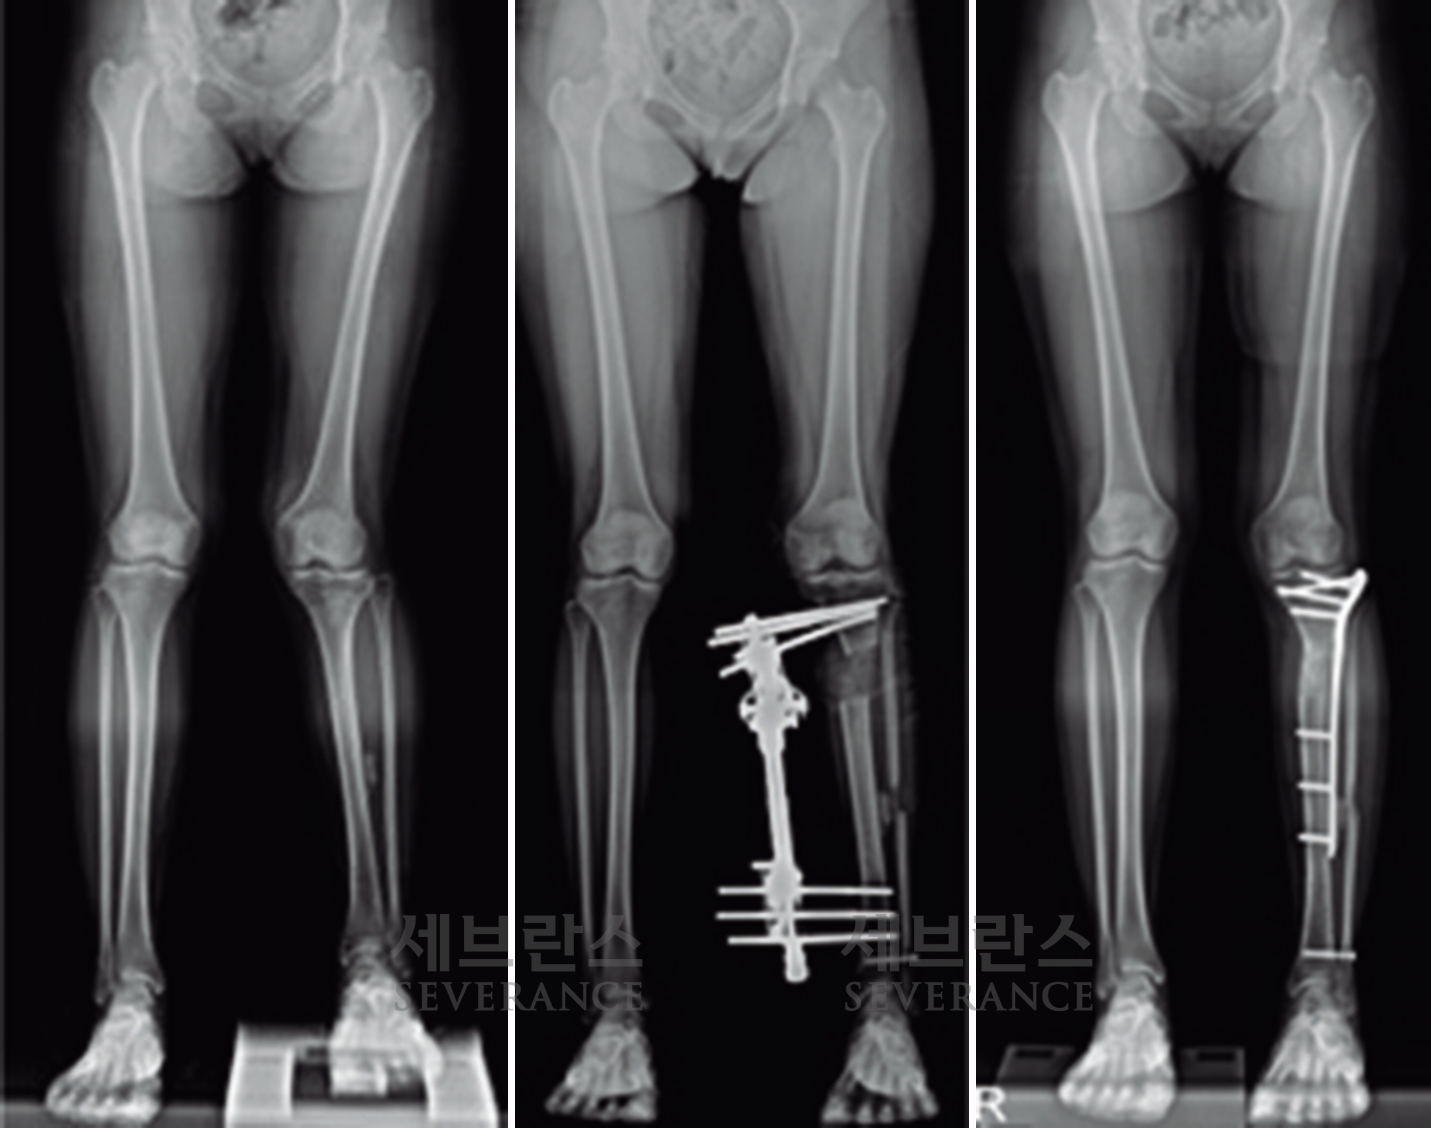

- 절골 교정술

성장이 끝난 환자나 변형이 심한 경우에는 절골 교정술이 효과적입니다. 이 수술은 뼈를 잘라 바른 위치로 되돌린 뒤 금속 장치로 고정하는 방식으로, 수술 직후 곧바로 교정 효과를 볼 수 있습니다. 그러나 절골된 뼈가 단단히 붙을 때까지 약 2-3개월이 소요되며, 그동안은 목발 보행 등 활동에 제약이 따릅니다.

구루병으로 발생한병적 내반슬(O다리) 변형에 대해

절골 교정술을 시행한 환아